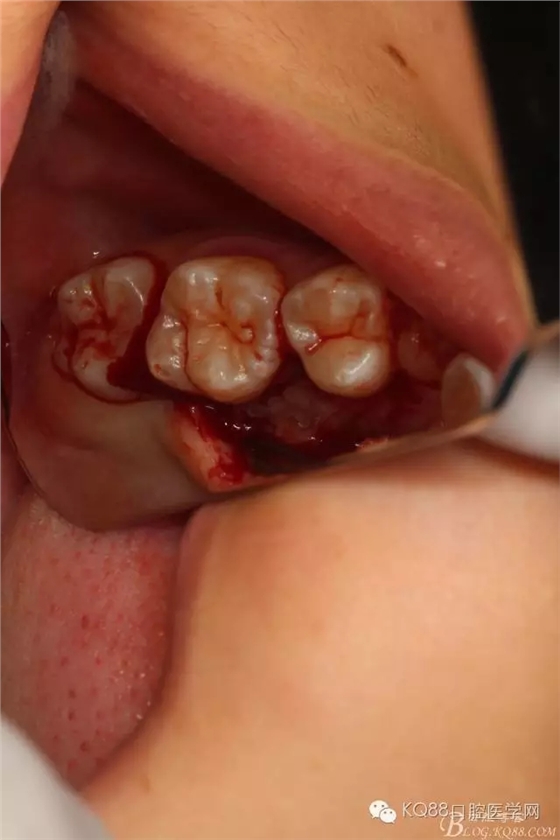

圖14.25的牙冠被挺松至齦緣處

圖15.順利拔除25,然后行頰側(cè)與腭側(cè)雙乳頭懸吊縫合,手術(shù)完畢